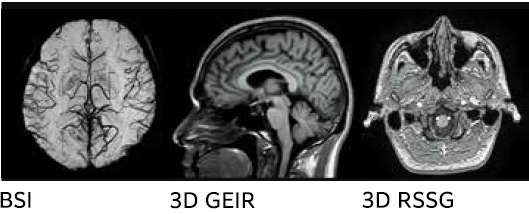

IP-RAPID hem yüksek görüntü kalitesi hem de daha kısa tarama süresi sağlar

IP-RAPID, görüntü kalitesini korurken tarama süresini azaltabilen bir teknolojidir.

Yetersiz örnekleme ve yinelemeli rekonstrüksiyonu birleştirerek, çeşitli bölge ve işlevlerle bir araya getirilebilir.

SNR ve uzamsal çözünürlük de tarama süresi korunarak iyileştirilebilir.